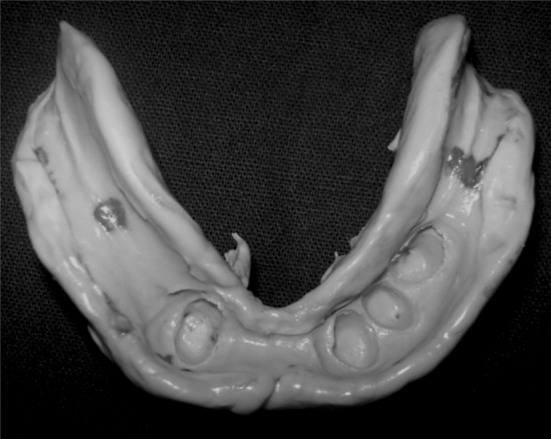

Fig. 9.

Definitive cast

Fig. 10.

Gypsum dummy (above dark line) was fabricated on the top of the keepers attractive surface of the cast